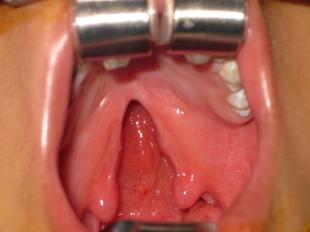

Cleft Palate Surgery - Before and After

Kung Plastic Surgery offers cleft palate surgery for residents of Chevy Chase, MD and Washington, DC. Cleft palate surgery closes the palate in order to restore the normal functions of the mouth with regard to eating and drinking, as well as enhance the development of the patients’ normal speech. Please enjoy these before and after pictures of cleft palate surgery.